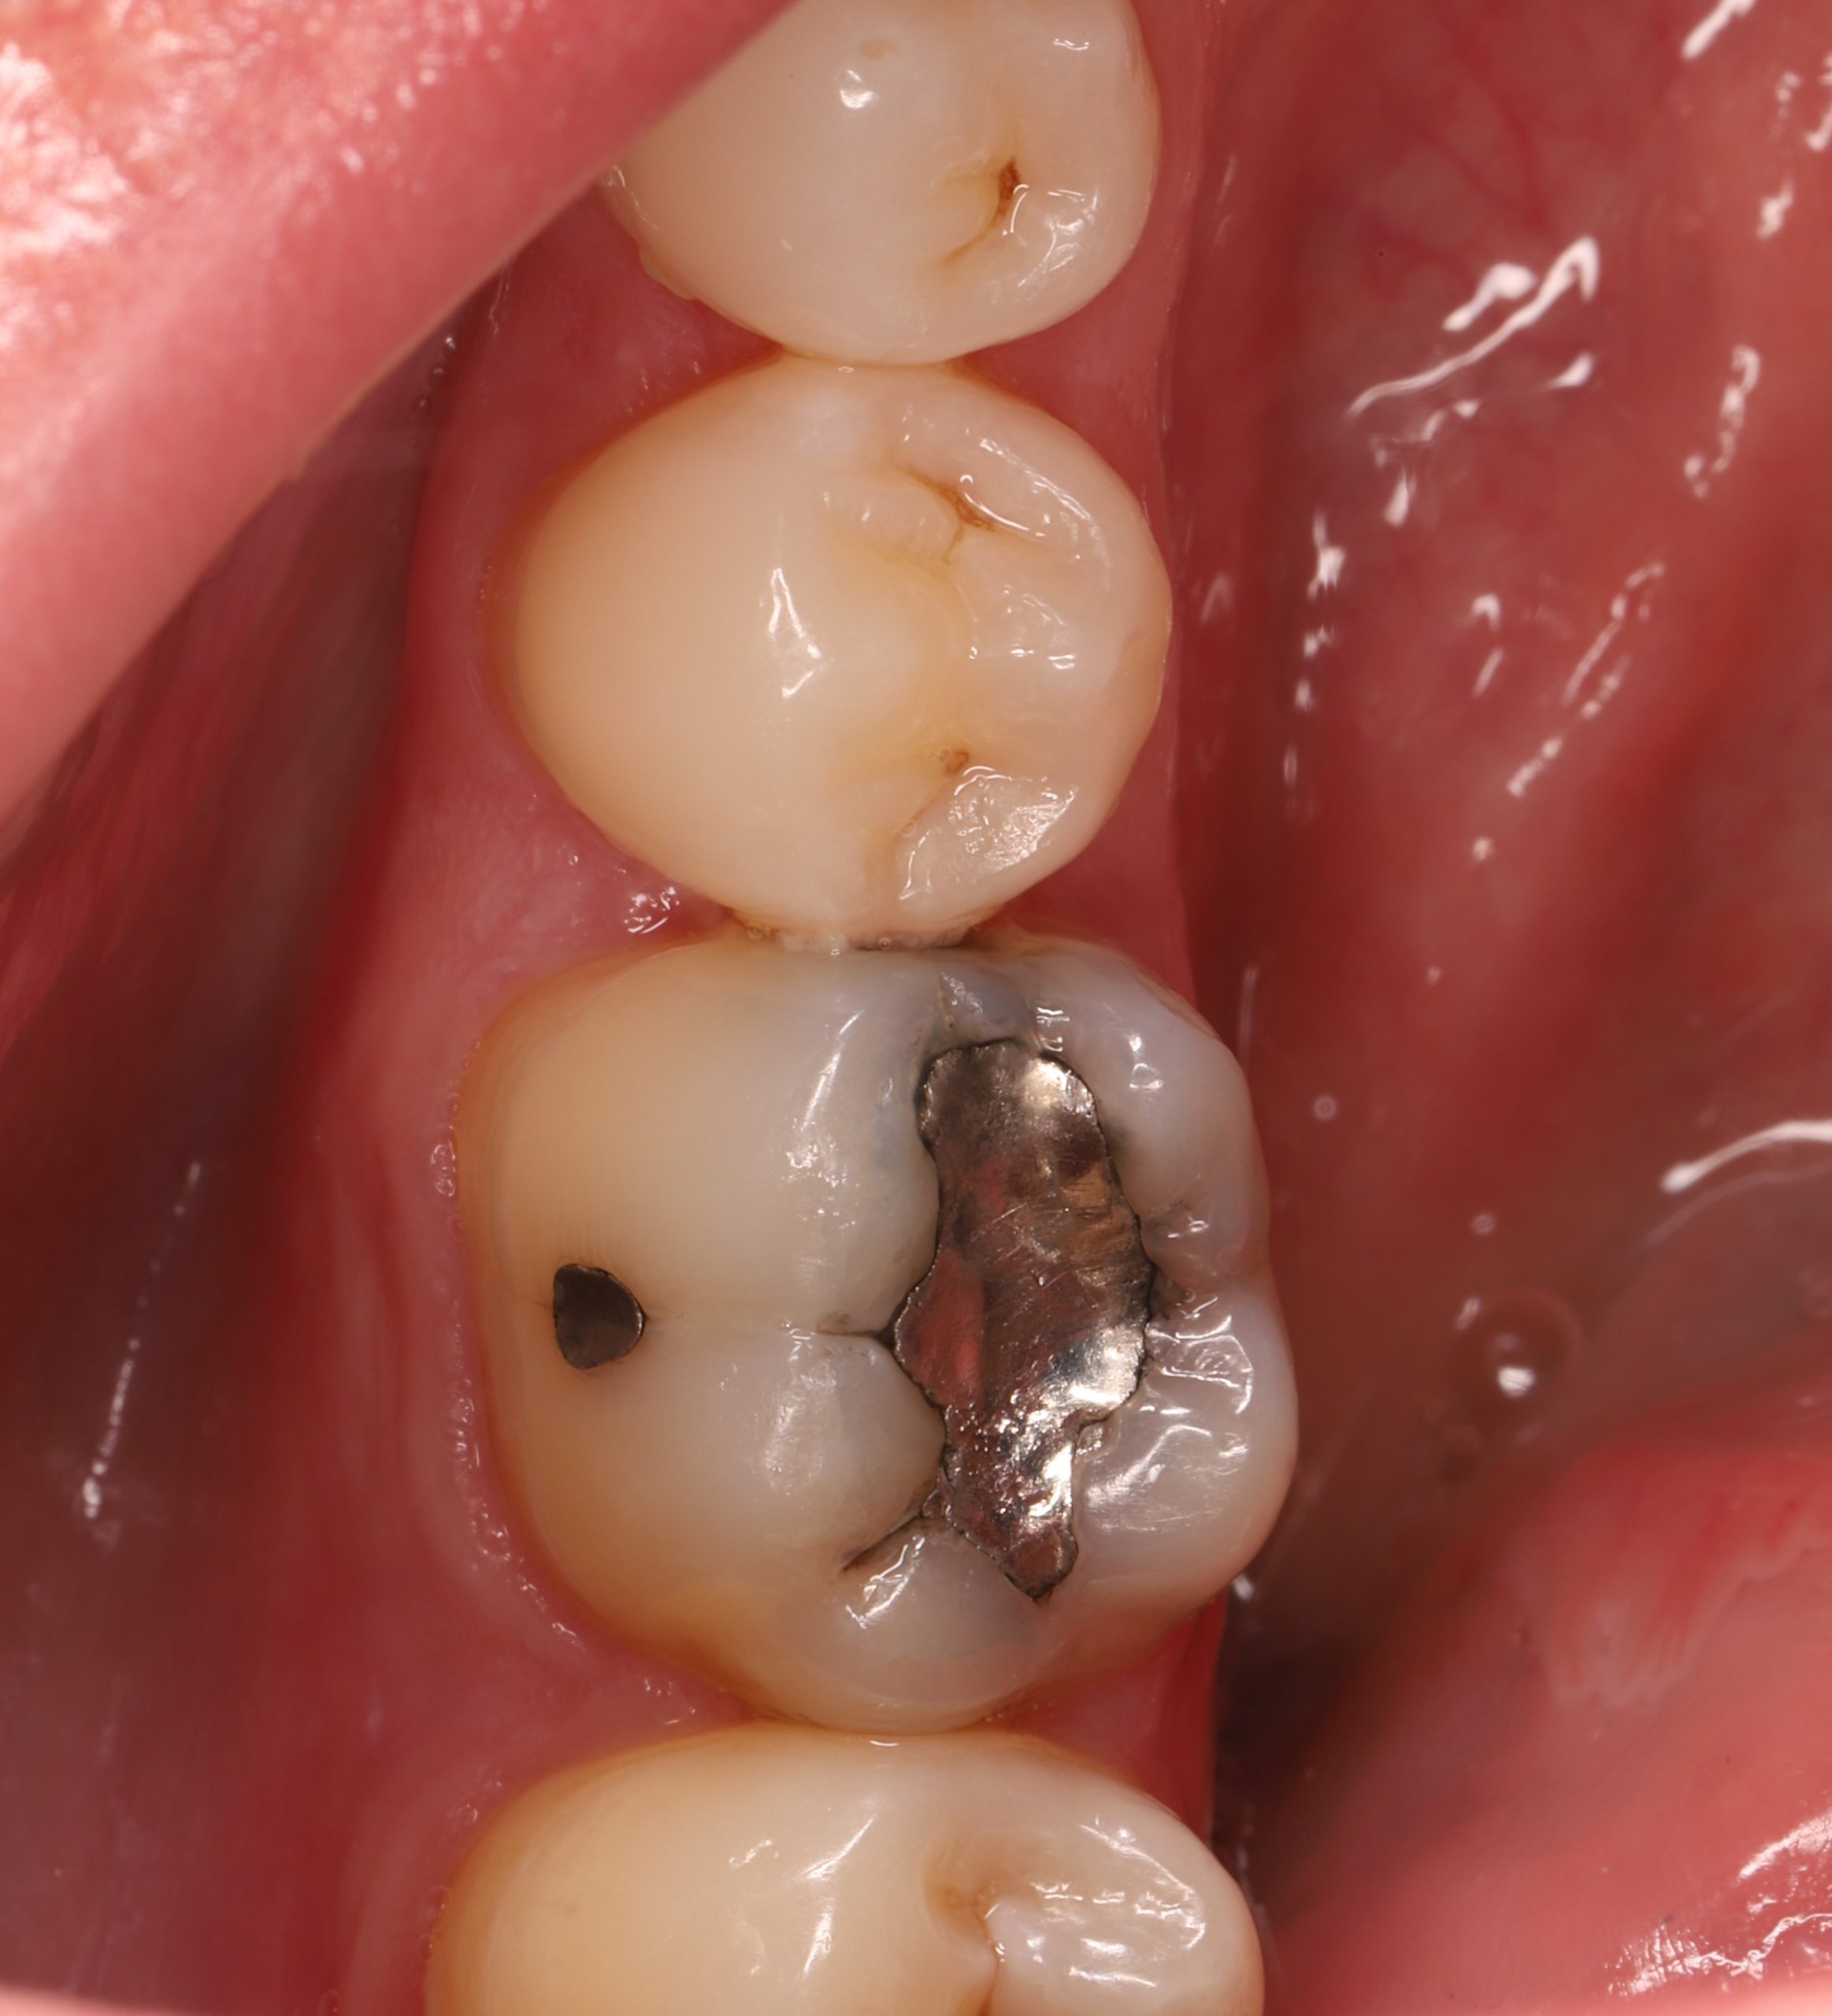

We remove weakened or decayed tissue and clean the area thoroughly. The goal is to preserve as much healthy structure as possible.

• replacing old metal fillings with a tooth-coloured option

A specialised adhesive is applied to create a secure link between your tooth and the composite. Strong bonding prevents leakage, improves longevity, and protects the tooth.